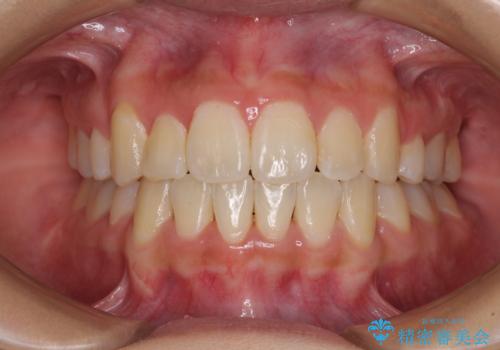

移動量が多かったため、治療期間は通常より半年~1年ほど長くかかりましたが、上下の正中をほぼ同じ位置にまで移動させることができました。